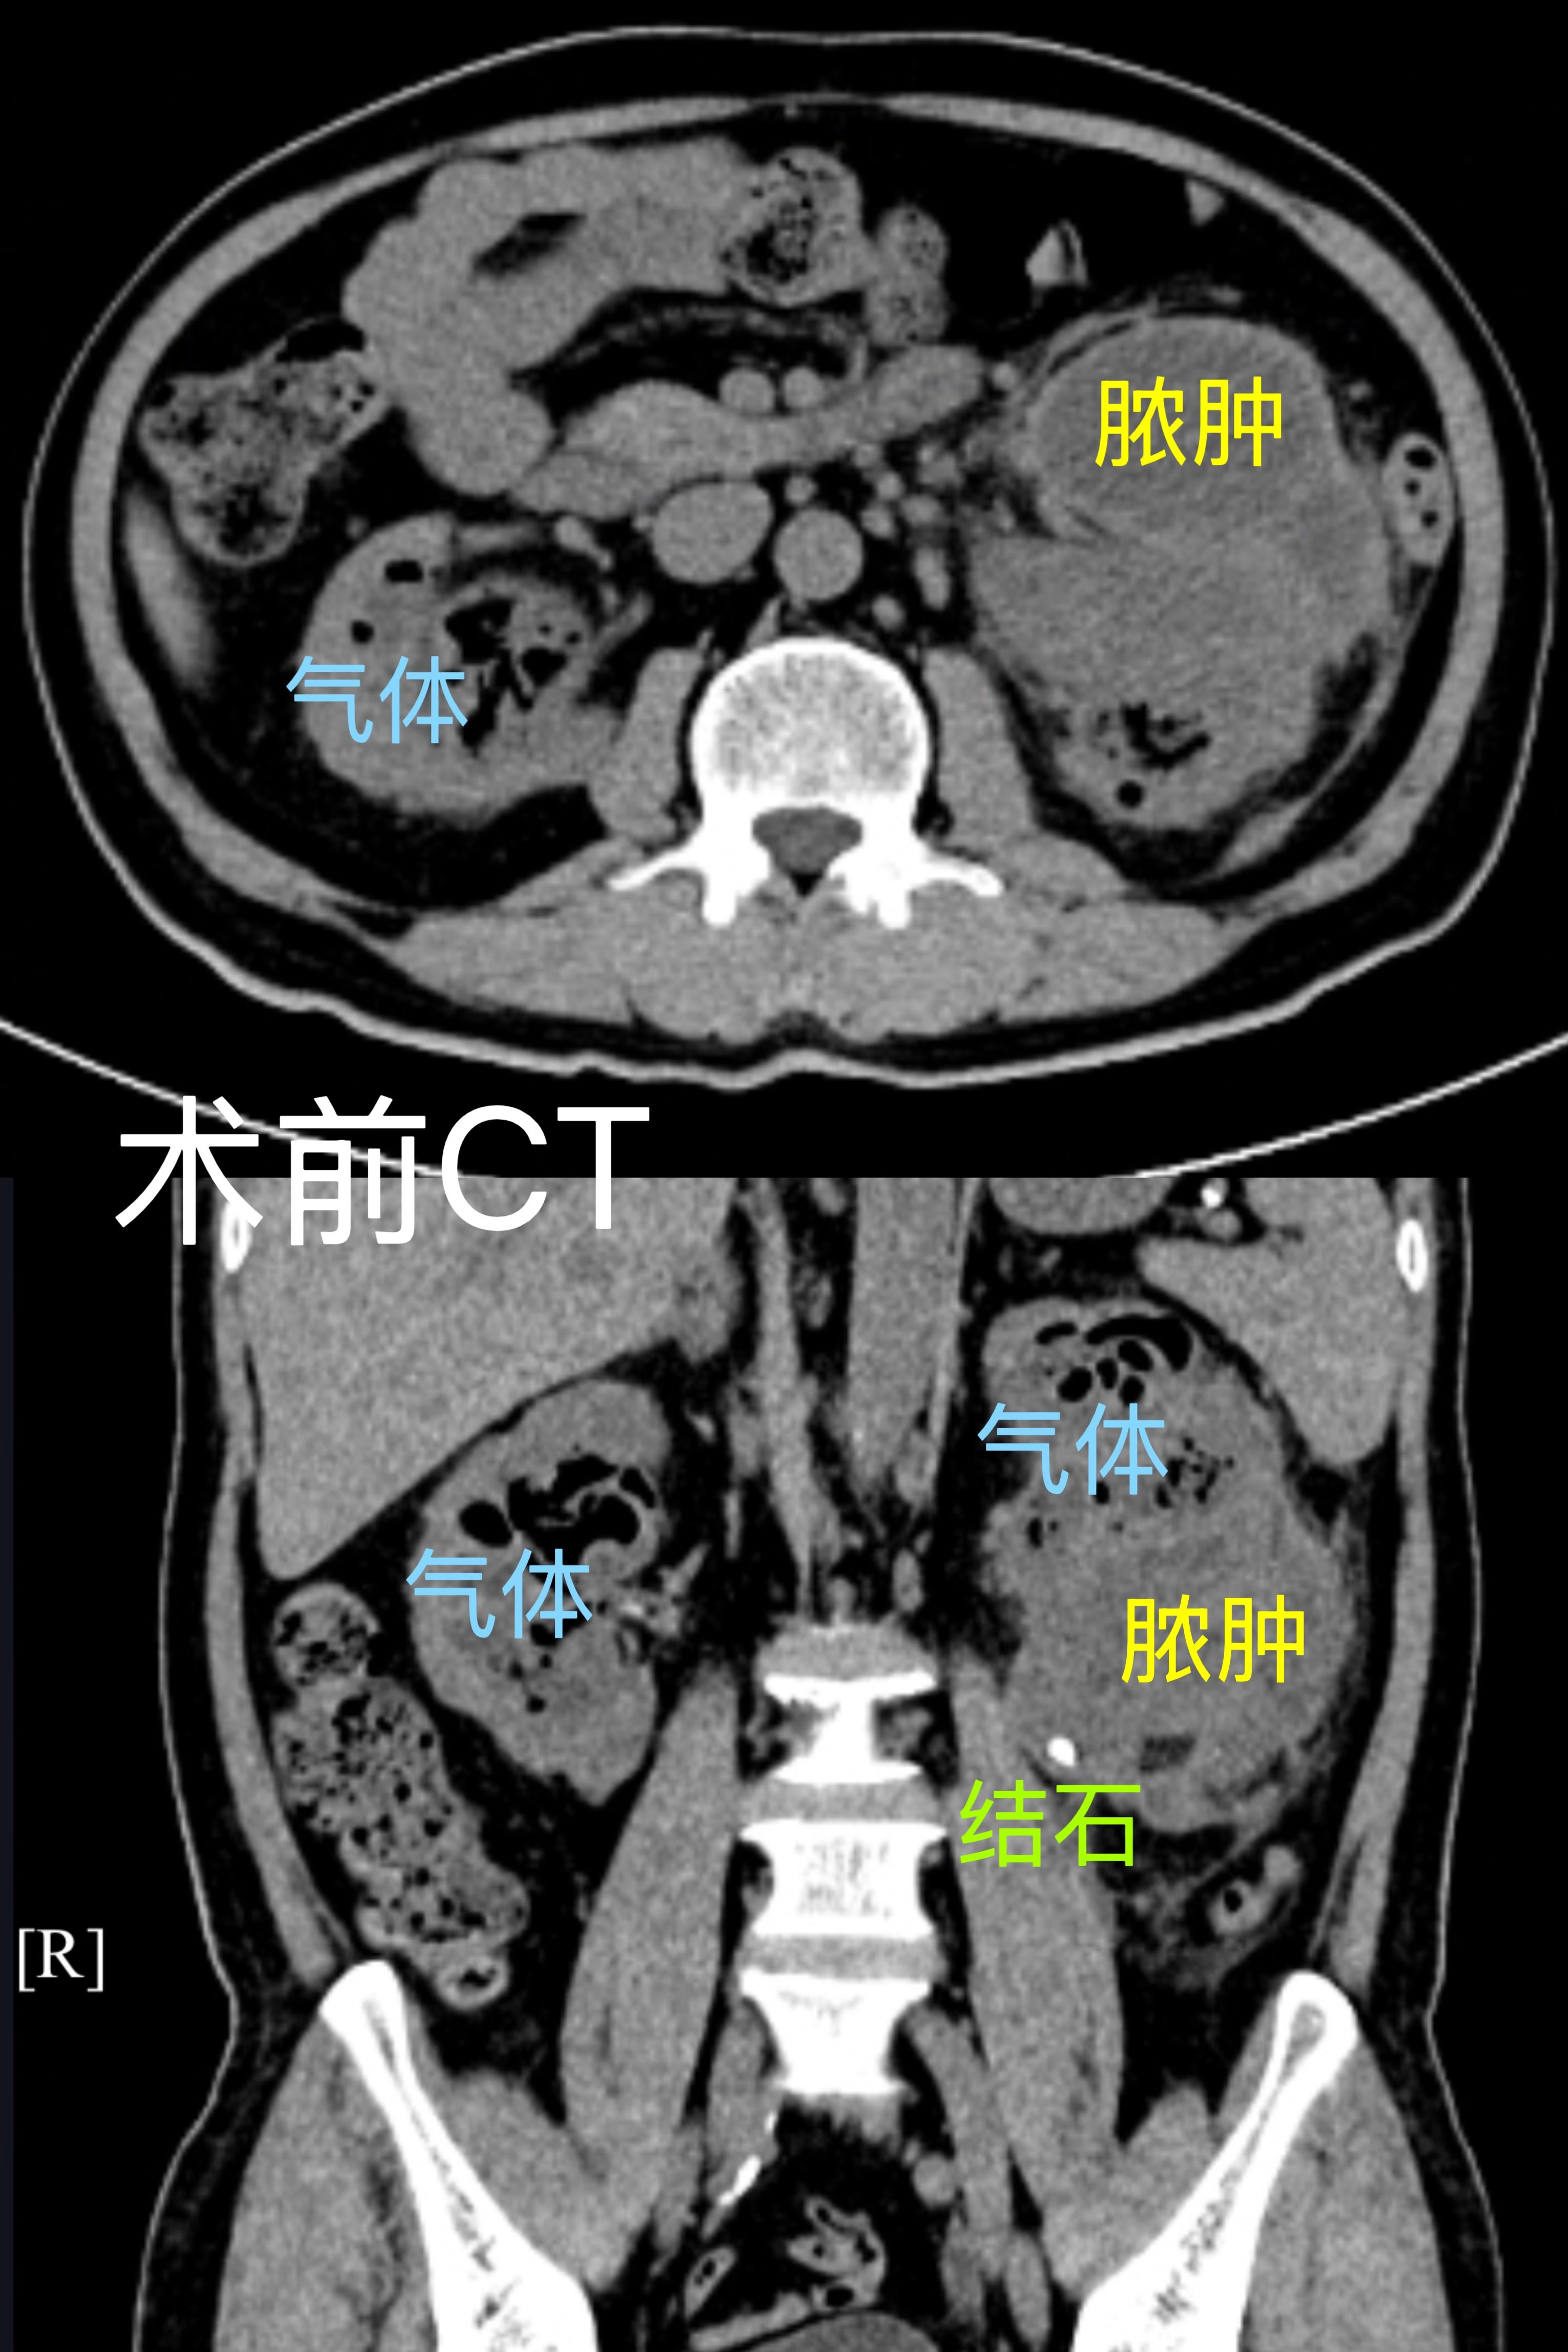

该患者为老年男性,病情复杂且凶险,确诊气肿性肾盂肾炎的同时,合并糖尿病、肾功能不全,且有心脏支架置入史,长期口服氯吡格雷和阿司匹林,入院尿培养提示真菌感染。气肿性肾盂肾炎是临床死亡率极高的泌尿系统急症,病情进展快,极易诱发感染性休克,再加上患者多重基础病症,救治难度极大。

随后,团队顺利为患者实施双侧经皮肾镜手术+双侧输尿管DJ管置入术+左肾周脓肿引流术,术中彻底清除肾内大量脓苔以及结石,术后有效引流脓性尿液,全程操作精准高效。术后患者生命体征平稳,未出现感染性休克、出血等并发症,肾功能明显好转,肌酐从术前316mmol/L降至153mmol/L,救治效果显著。